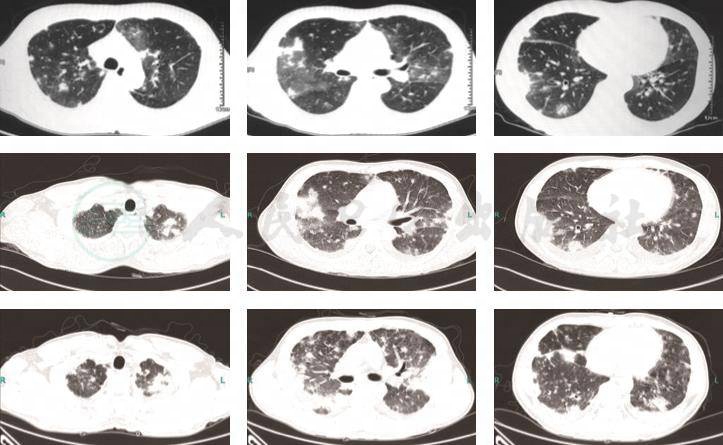

1.入院后改用莫西沙星联合伏立康唑或卡泊芬净(4月18日~5月1日)抗细菌、真菌治疗,4月22日~5月1日诊断性抗结核治疗(异烟肼、利福平、乙胺丁醇、吡嗪酰胺)。间断输入同型浓缩红细胞纠正贫血。患者仍有发热,呼吸困难进一步加重,5月4日复查胸部CT示双肺病变较前进一步加重(图5)。

2.5月4日肺穿刺活检病理结果回报考虑机化性肺炎,开始予以甲泼尼龙(80mg/d×3天后改为40mg/d维持)抗感染治疗,同时停用抗真菌治疗。患者体温逐渐下降至正常(5月7日体温恢复正常),呼吸困难症状好转。5月15日(激素治疗10天)复查胸部CT示双肺病灶较前明显吸收好转(图5)。

患者2017年6月复查胸部CT示双肺病变进一步吸收好转。

图5 胸部CT

(由上至下分别是2017年5月4日,2017年5月15日)